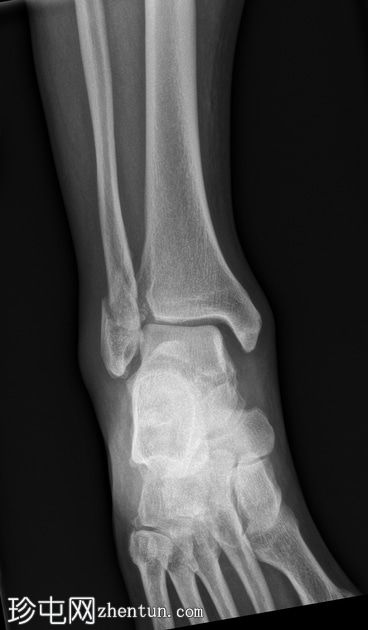

2.jpg

侧面

腓骨下端轻度螺旋形骨折,位于下胫腓联合水平(Weber B),骨折移位,伴有轻度软组织肿胀。

踝关节内侧间隙增宽6毫米(正常值<4毫米),胫腓间隙增宽,胫腓重叠减少,这些表现提示胫腓联合损伤和踝关节不稳定。

踝关节内侧软组织阴影,提示内侧副韧带损伤。

后踝(踝骨)骨折轻微移位。

可见腓籽骨。

足底跟骨骨刺。

可见跟腱末端钙化性病灶。